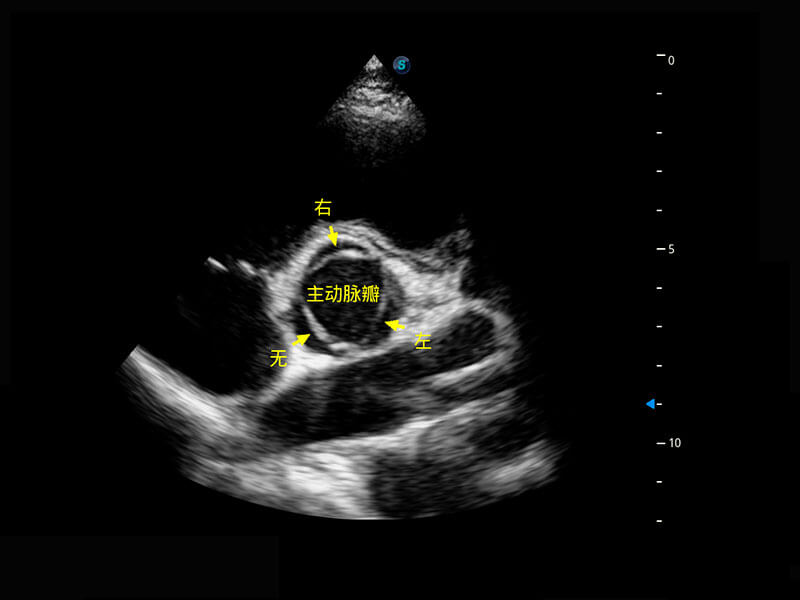

乳腺超声 / 新生儿

P60搭载宽频带线阵探头、宽景成像、弹性成像技术,为您提供乳腺应用方案。P60支持高频相控阵探头、线阵探头、腹部高频探头、腹部微凸探头等,丰富的探头群搭载敏感的彩色血流成像,适用于新生儿多种脏器检测要求,满足新生儿筛查需求。

• 新生儿心脏